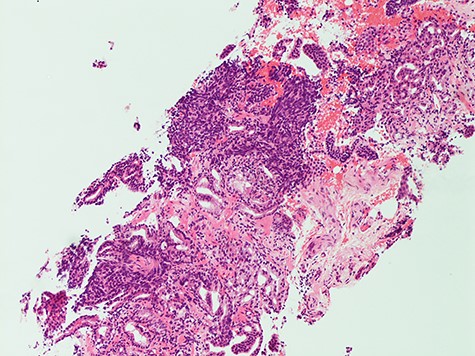

Histology from trans-rectal ultrasound (TRUS) biopsy of the prostate showed a conventional microacinar type prostatic adenocarcinoma of Gleason score 4 + 4 = 8 with an intermingled component of SCC, composed of cohesive sheets of small cells with scant cytoplasm, hyperchromatic nuclei and nuclear molding with increased mitotic activity (Fig. 2). The cytomorphology was similar to the neck FNA. The small cell component showed positive staining for neuroendocrine markers Synaptophysin and CD56. The Ki-67 index was 70%. PSA showed scattered positivity. Overall, the features were consistent with a mixed microacinar adenocarcinoma and SCC. Following the diagnosis from TRUS biopsy, PSA immunostain was carried out on the FNA material, which showed scattered positivity.

The diagnosis of SCCP is based on morphological features defined in the World Health Organization (WHO) classification criteria of pulmonary neoplasms (WHO 2015). From a diagnostic point of view, it is important to recognize this rare variant and not misdiagnose it for a high-grade Gleason 5 pattern, as there is a morphological overlap [5]. In cases where there is morphologic concern for neuroendocrine carcinoma (sheet-like architecture, nuclear molding and scant cytoplasm), it is essential to perform immunohistochemistry with neuroendocrine markers and PSA. In our case, the SCC component was strongly positive for neuroendocrine markers Synaptophysin and CD56 with focal positivity for PSA. In the conventional component it was the reverse; strong PSA positive and very focal NE scattered cells (Figs 3 and 4). This is in line with the literature findings [5, 8].